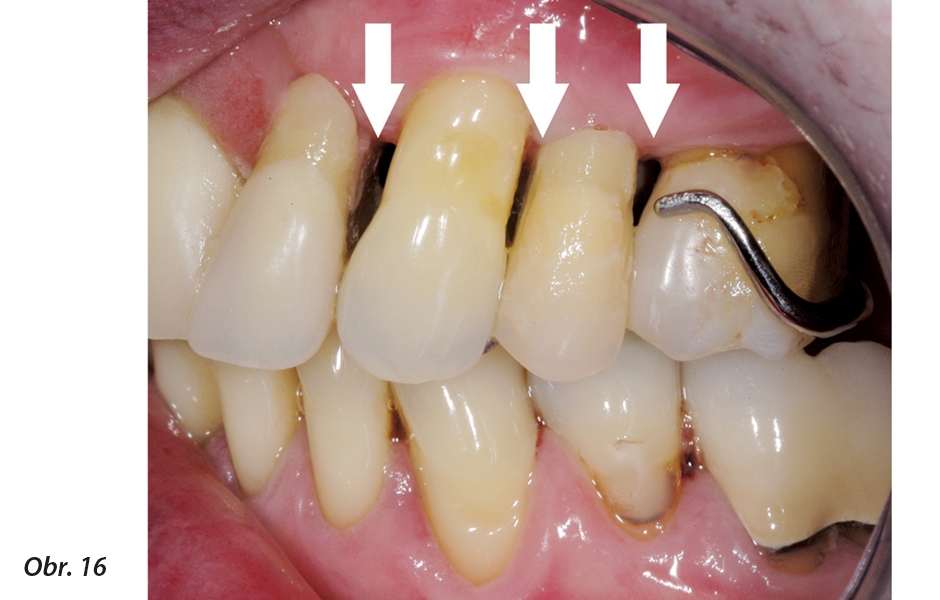

Prvky zubní náhrady musí být navrženy tak, jak je vidět na obr. 15, aby redukovaly nebezpečí poranění tkání a současně byla možná úprava slizniční plochy ČSN.

U vyobrazených příkladů horní a dolní ČSN jsou hlavní spojovací prvky mimo oba pilířové i nepilířové zuby a pod body kontaktu mezi prvním zubem náhrady a sousedním přirozeným pilířovým zubem je aproximálně prostor (obr. 16). První zub náhrady je vytvarován jako mezičlen můstku, aby napodobil přirozený aproximální prostor. Umožňuje to také přístup pro mezizubní kartáčky, a to i při nasazené zubní náhradě (obr. 17).

Požadavek na hygienický design vyžadující optimální úpravu slizniční plochy ČSN v oblasti pilířových i nepilířových zubů

Zuby v náhradě z obou stran přirozeného horního levého špičáku jsou vytvarovány tak, aby byly zachovány čistitelné mezizubní prostory

Aproximální prostor nad bodem kontaktu mezi přirozeným pilířem a prvním zubem náhrady umožňuje zasunutí mezizubního kartáčku. To pomůže účinnému vyčištění distální strany přirozeného zubu.